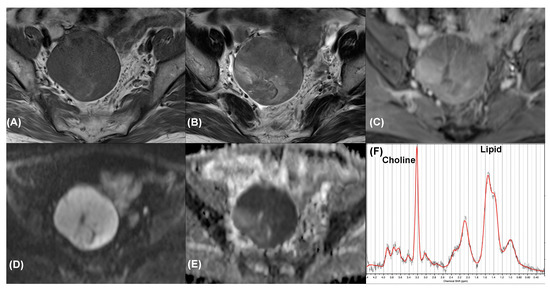

| 9 | Endometrioid carcinoma | Yes | 4 | TP | TP |

| 10 | Endometrioid carcinoma | Yes | 4 | TP | TP |

| 11 | Serous cystadenocarcinoma | Yes | 4 | TP | TP |

| 12 | Serous cystadenocarcinoma | Yes | 4 | TP | FN |